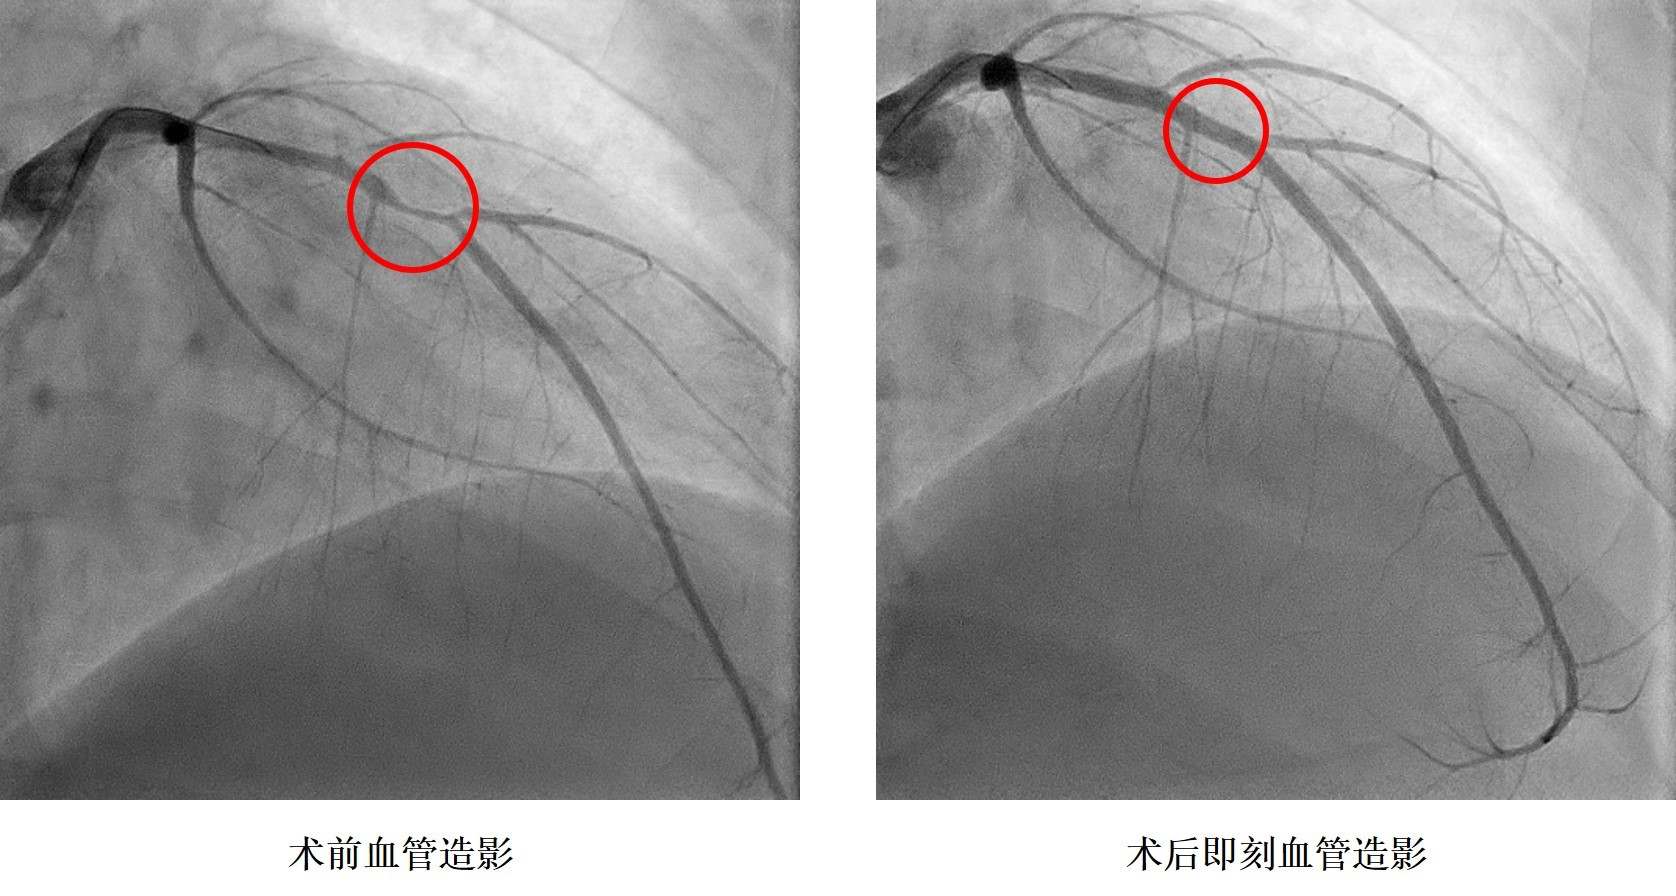

小浩在2019年9月6日晚飯時(shí)突感胸痛、胸口悶、呼吸困難,立即前往湖南省人民醫(yī)院胸痛中心就診,診斷為急性心肌梗死,小浩被送往介入手術(shù)室,進(jìn)行急診造影后發(fā)現(xiàn)冠狀動(dòng)脈血管嚴(yán)重狹窄,需要在體內(nèi)植入心臟支架。據(jù)了解小浩從14歲就開始了抽煙,還發(fā)現(xiàn)了高血壓,血壓最高200mmHg,卻一直沒(méi)有規(guī)律服藥治療。16歲讀完技校后的他開始過(guò)上了淘寶電商的生活,生活日夜顛倒,夜間修圖、改片,并頓頓燒烤,白天睡覺(jué),缺乏運(yùn)動(dòng),這樣的生活維持了兩年本次。入院后同時(shí)發(fā)現(xiàn)了糖尿病,這一系列原因是導(dǎo)致小浩發(fā)生心肌梗死的罪魁禍?zhǔn)住?/p>

孩子還這么小,人生剛剛開始就要帶上心臟支架生活嗎?心內(nèi)科鄭昭芬主任組織團(tuán)隊(duì)進(jìn)行了會(huì)診,建議植入生物可吸收心臟支架!拔覀儽緛(lái)不愿意植入心臟支架,但聽(tīng)說(shuō)有一種新型的心臟支架在植入體內(nèi)后幾年就能降解,就接受了!痹谡鞯眯『票救撕图胰送夂,心內(nèi)三科潘宏偉主任利用血管內(nèi)超聲指導(dǎo),順利植入生物可吸收心臟支架,拆除了小浩體內(nèi)的“炸彈”。